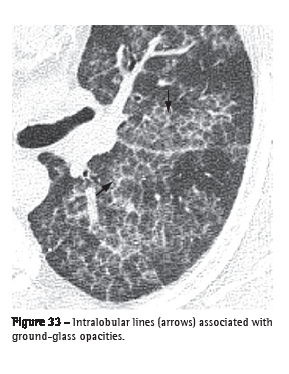

Intralobular lines (linhas intralobulares)

Intralobular lines are seen on HRCT scans as thin linear images within the secondary pulmonary lobule. When numerous, they can have a fine reticular aspect (Figure 33). This finding can be seen in different conditions, especially in cases of fibroses (e.g., usual interstitial pneumonia) and diseases associated with the crazy-paving pattern (e.g., alveolar proteinosis).(3,54)

See also Reticular pattern and Crazy-paving pattern.